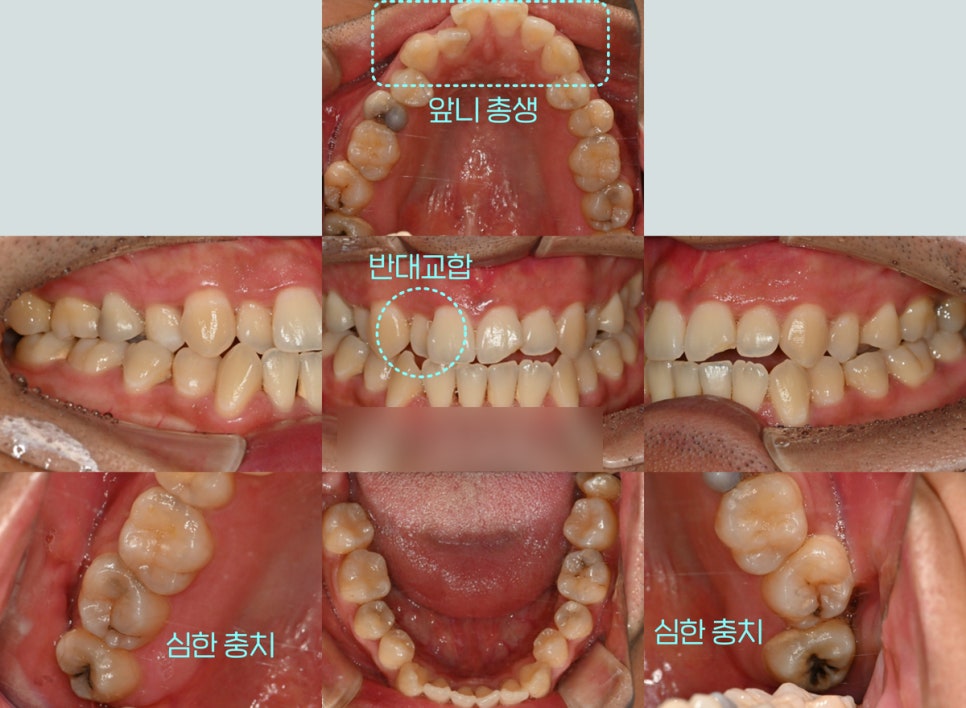

초진 사진을 확인해 본 결과

심한 총생과 반대교합 그리고

검게 썩어 있는 어금니를 볼 수 있었습니다.

삐뚤어진 배열로 인해 관리가

어려웠던 것으로 확인되는데요.

절단 교합까지 함께 확인되어

이대로 내버려두었다간

턱관절이나 교합에도 좋지 않은

영향을 끼칠 거란 판단이 들었습니다.